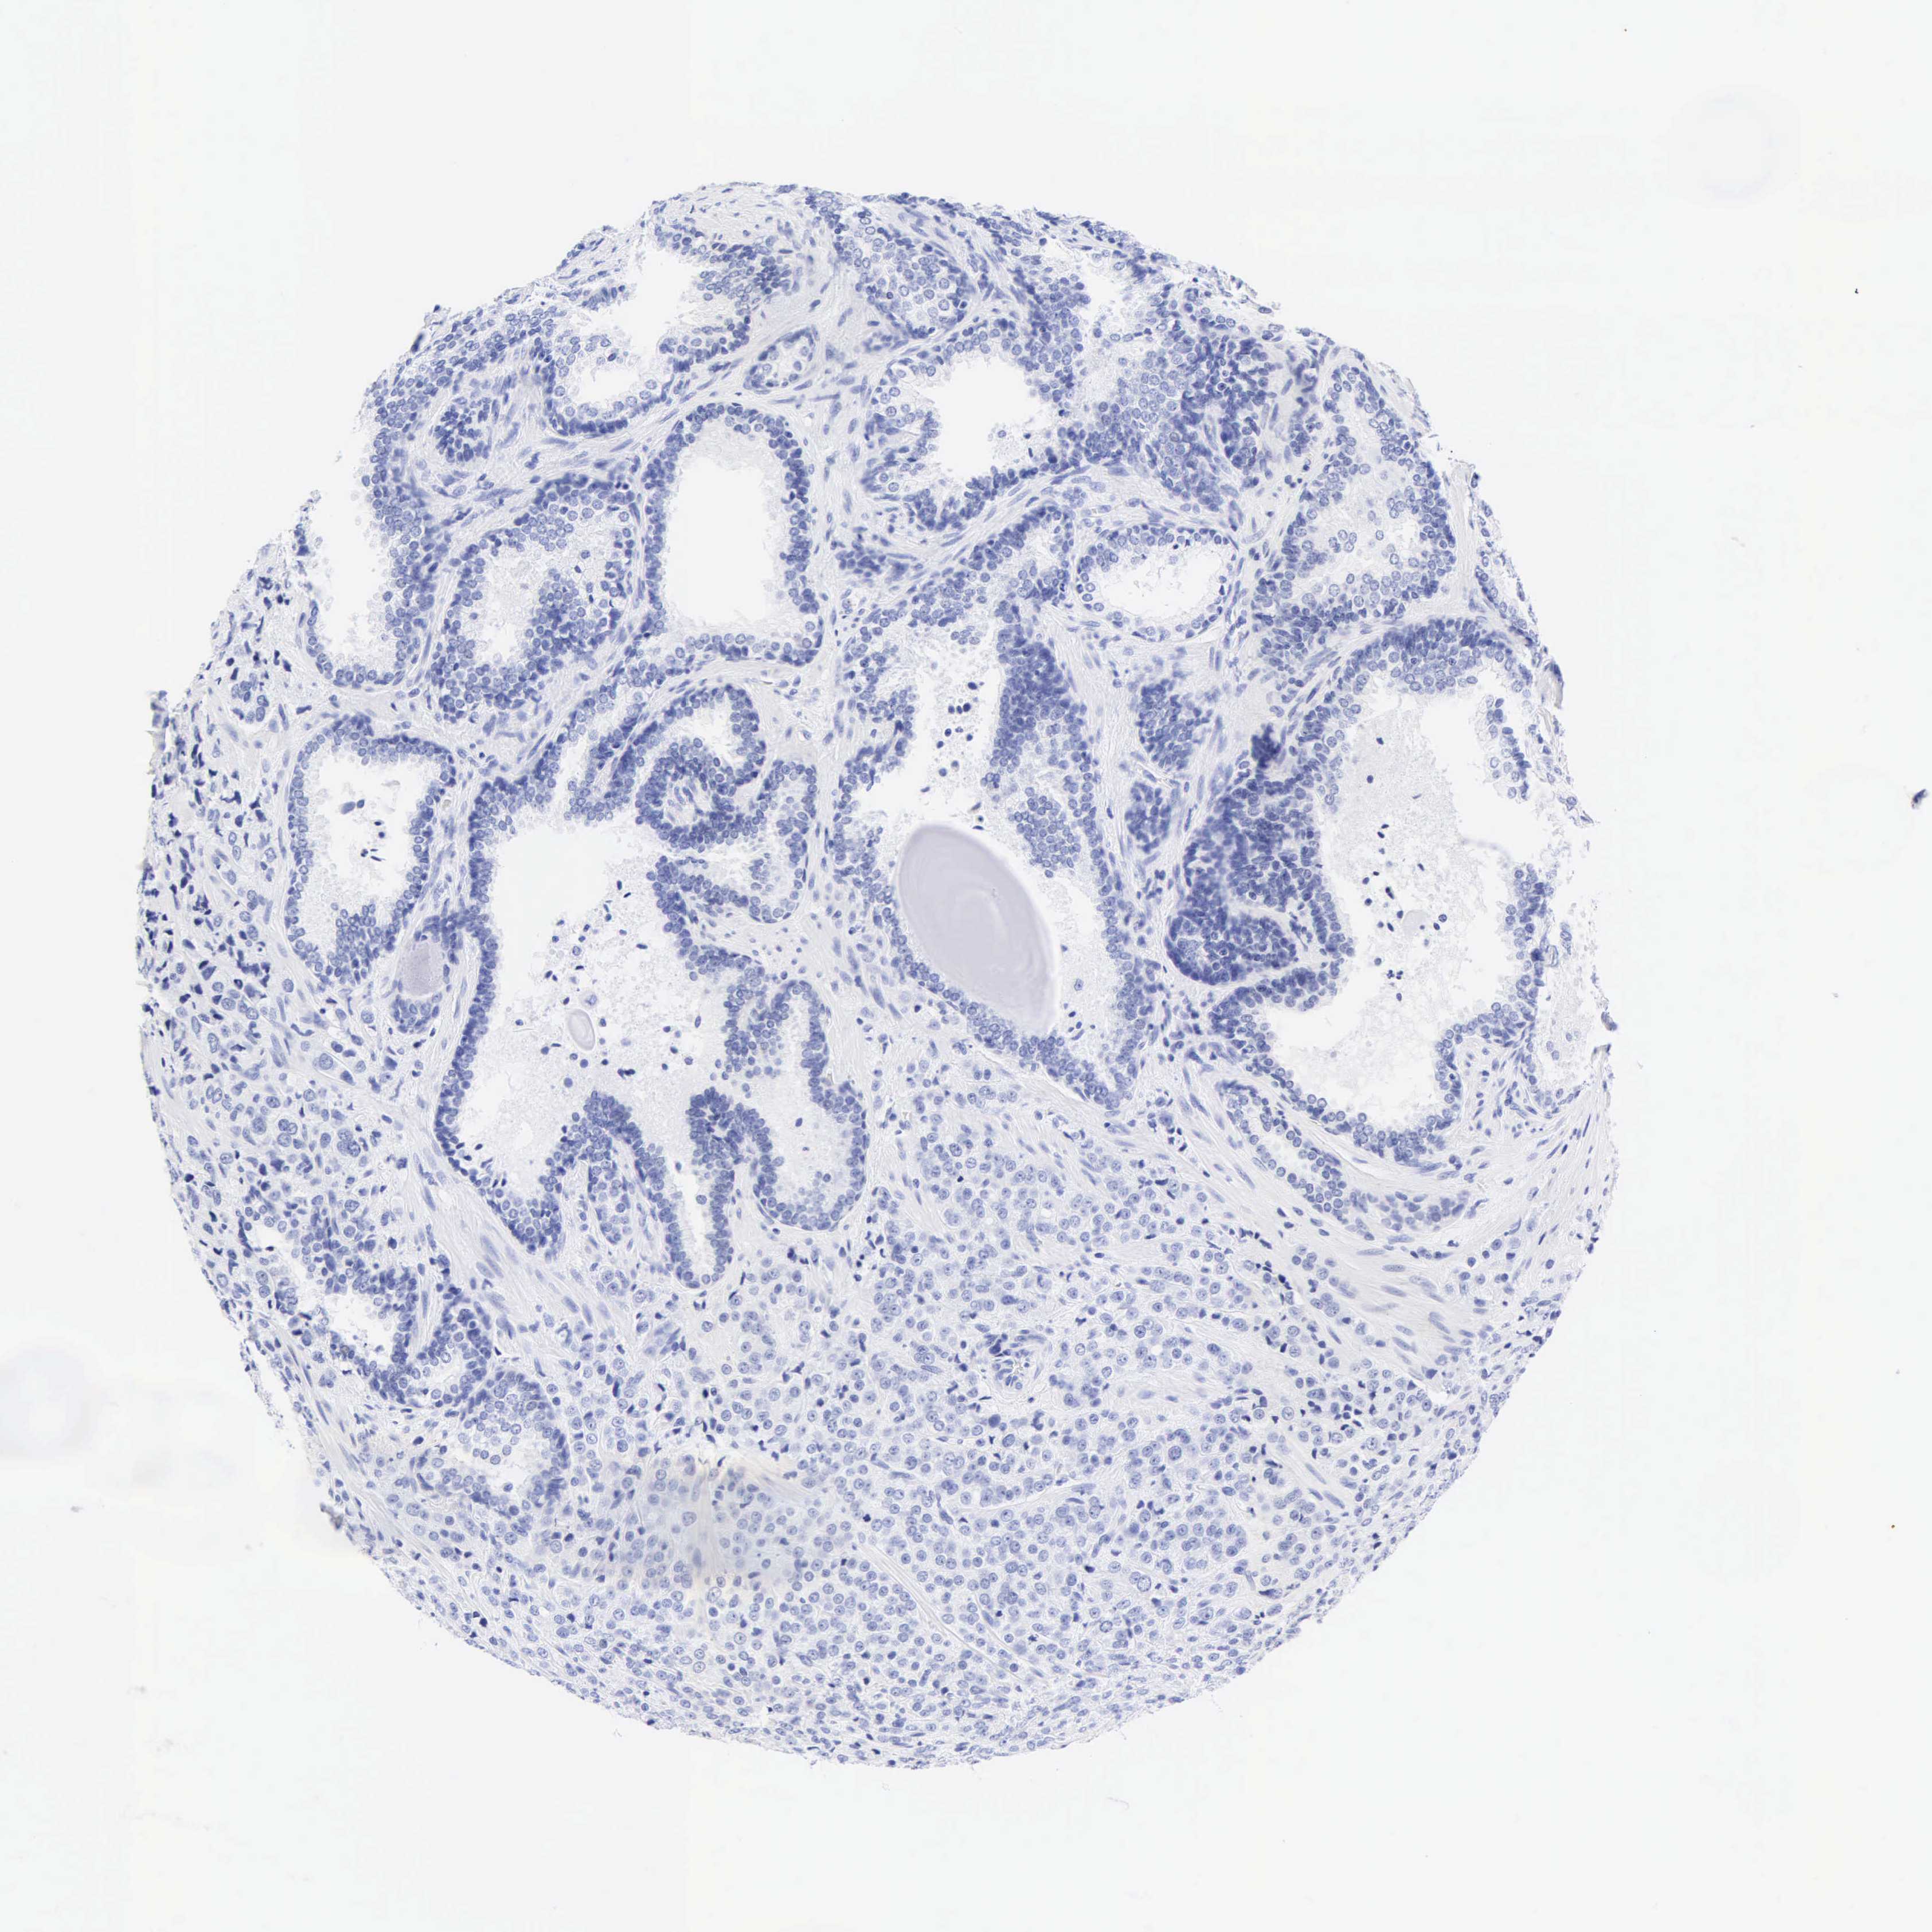

PROSTATE CANCER - Protein expressioni

A mouse-over function shows sample information and annotation data. Click on an image to view it in a full screen mode. Samples can be filtered based on level of antibody staining by selecting one or several of the following categories: high, medium, low and not detected. The assay and annotation is described here.

Note that samples used for immunohistochemistry by the Human Protein Atlas do not correspond to samples in the TCGA dataset.

Antibody stainingi

Antibody staining in the annotated cell types in the current human tissue is reported as not detected, low, medium, or high, based on conventional immunohistochemistry profiling in selected tissues. This score is based on the combination of the staining intensity and fraction of stained cells.

Each image is clickable and will lead to virtual microscopy that enables deeper exploration of all samples and also displays staining intensity scores, fraction scores and subcellular localization as well as patient and tissue information for each sample.

Antibody HPA024309

Antibody HPA024684

Antibody HPA027236

Antibody CAB000032

Staining

High

Medium

Low

Not detected

Intensity

Strong

Moderate

Weak

Negative

Quantity

>75%

75%-25%

<25%

None

Location

Nuclear

Cytoplasmic/membranous

Cytoplasmic/membranous,nuclear

Adenocarcinoma, High grade

Adenocarcinoma, Low grade

Adenocarcinoma, Medium grade